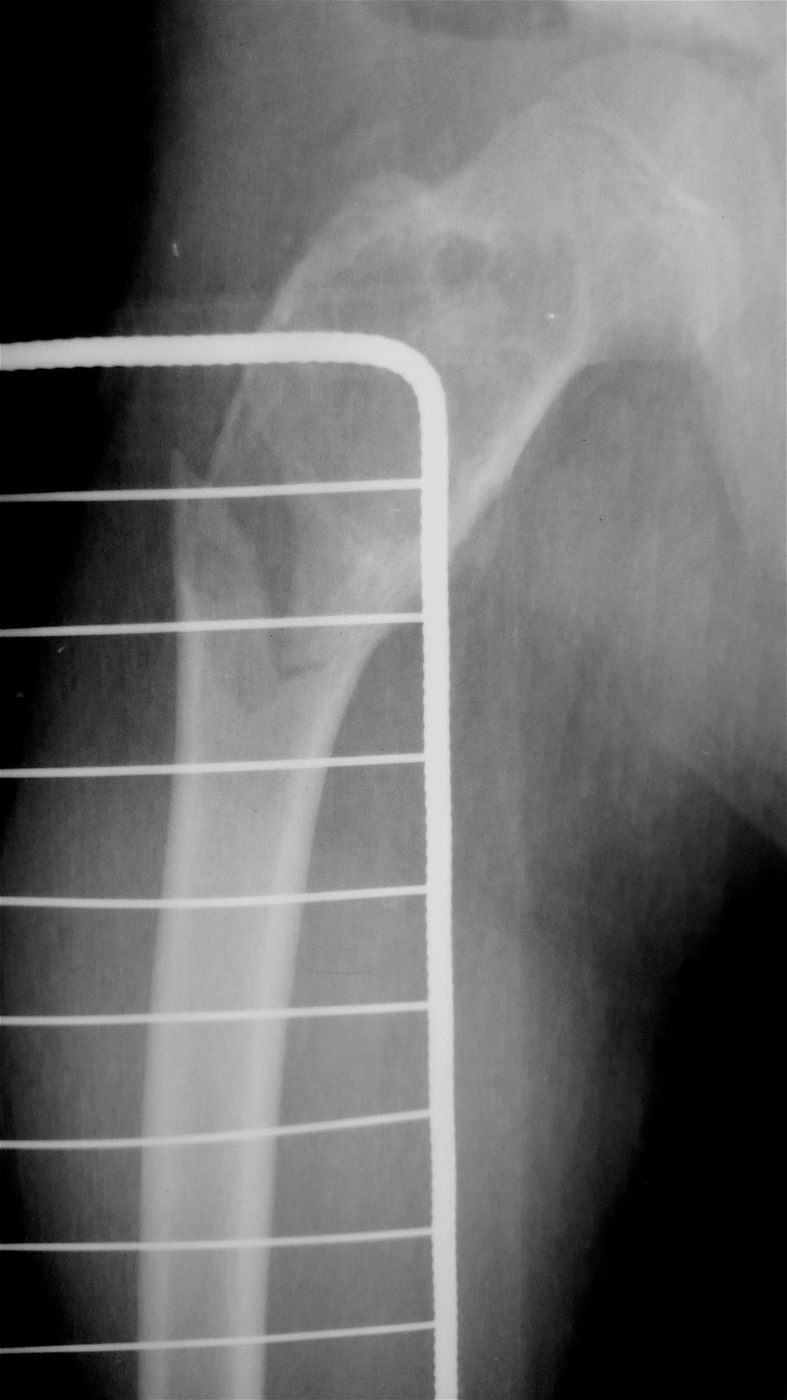

Закрытый, паталогический перелом в подвертельной области правой бедренной кости со смещением, на фоне аневризмальной костной кисты.

Выполнена резекция с аллопластикой губчатыми и кортикальными биоимплантатами "Лиопласт".